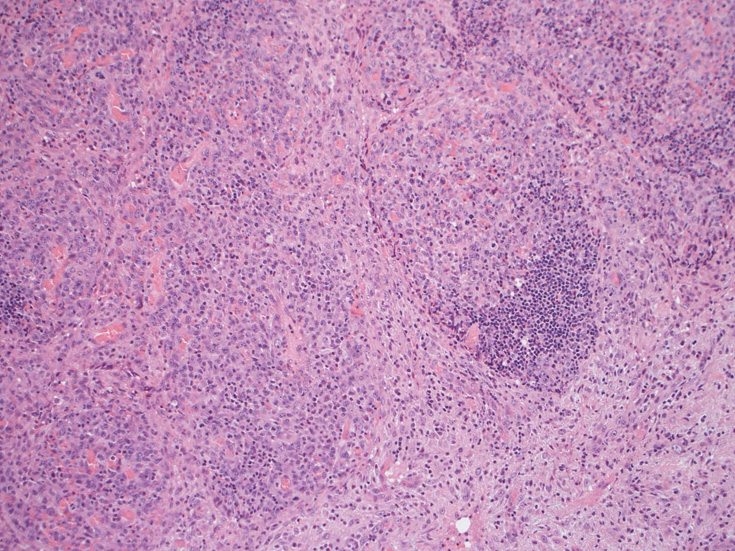

腹膜脂肪組織内から生検されたリンパ節は基本構造を失っている。低倍率のHE所見では異型細胞が不鮮明な結節構造を形成して増殖している。一次リンパ濾胞を腫瘍細胞が置換しているように見える所見がある。

高倍率x400では, 増殖細胞はcentroblastに似て複数の明瞭な核小体をもった淡明な大型類円ないし卵円形核を持っている。核分裂像が多い。この症例では多型はめだたない。典型的な腎臓型のくびれた核を持つ細胞などはない。ALKの形態的variant症例と考えられるが, 化学療法後の再発による影響も否定できない。